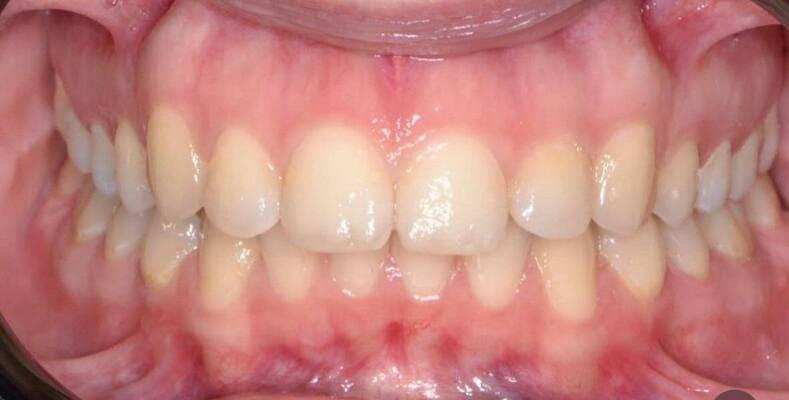

Пацієнт 2 років, уражено десять зубів, шість із яких потребують покриття коронками. В зв’язку зі значним об’ємом та складністю лікування прийнято рішення про лікування в умовах анестезіологічного забезпечення. Раніше була спроба пролікувати ці зуби застарілими методами, які не тільки не є ефективними відносно лікування, а ще і додають дитині комплексів через характерне фарбування зубів. Через високи естетичні вимоги дитини і батьків було прийнято рішення покривати естетичними цирконієвими коронками, як передні так і бічні зуби. Через 2,5 години дитина без інфекції в порожнині рота, з відновленим здоров’ям та естетикою посмішки може кусати, жувати, посміхатись без болю та дискомфорту. Останнє фото через 2 роки після лікування, оскільки естетичні коронки в дитячій стоматології - це надійність, естетика та функція.